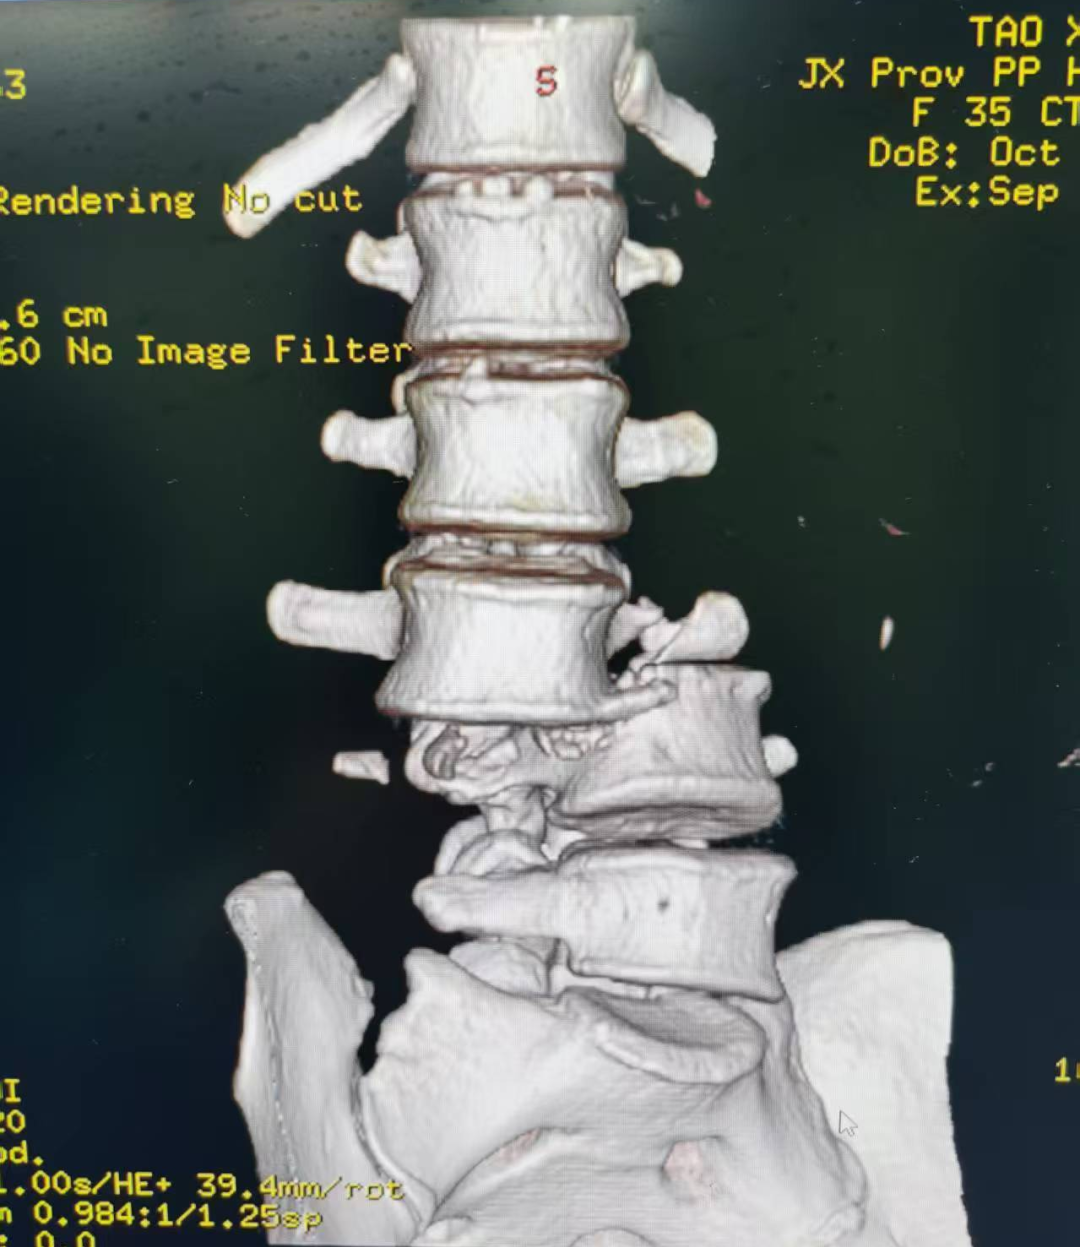

9月4日,共青城市的一条马路上,陶某在送孩子上学时被小汽车撞倒,巨大的冲击力让她的腰部像被重物砸中,下半身瞬间失去知觉。送到共青城市人民医院时,CT显示:腰3/4椎体骨折伴完全脱位,骨折块像一把锋利的刀,刺穿硬脊膜,死死压迫着马尾神经。当地医生明确告知需尽快手术,抢救神经功能,但由于当地医院不具备复杂脊柱手术条件,陶某通过江西省人民医院与共青人民医院骨科医联体绿色通道,被紧急转往省人民医院骨科进一步治疗。

患者腰3/4椎体完全骨折脱位